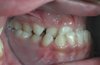

ÇAPRAŞIKLIK

Çenelerde dişler için yeterli yer olmadığında çapraşıklık görülür. Yeterli yer sağlamak için diş çekimi yapılabilir.